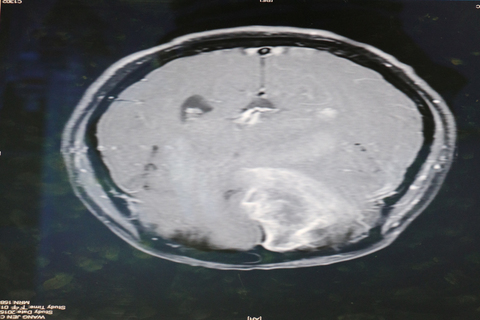

為清除位在大腦功能區附近的腫瘤,術中GPS導航,降低腦瘤切除風險。 (圖/嘉義基督教醫院提供)

【新唐人亞太台 2016 年 07 月 18 日訊】在醫界中,腦瘤切除被喻為最棘手的手術,如果稍有失準,就可能破壞神經系統,造成癱瘓。嘉義基督教醫院日前利用術中GPS導航,讓開腦手術更安全,大大減少手術無法預期的神經系統傷害,以及併發症及死亡率。

51歲的李女士經常頭暈不舒服,一天工作時突然左半身沒力,至嘉基檢查後發現是罹患乳癌併腦轉移。位於大腦右側頂葉運動區附近,由於腫瘤壓迫,導致左側肢體偏癱。嘉基神外醫療團隊利用術前立體定位導航系統,安全將腫瘤移除,術後病患左側肢體肌力顯著進步,能自行走路進食。

嘉義基督教醫院醫師陳昱豪表示:腦瘤切除手術十分棘手,稍有誤差就可能破壞神經系統,造成功能性問題。尤其是膠質瘤,邊緣非常不清楚,甚至顯微鏡下仍無法區分,這時後術中GPS導航系統-立體定位導航手術就非常的重要。

立體定位放射手術(伽傌刀或電腦刀)前先將影像與電腦結合,定位出腦瘤的位置及範圍,也可以在術中利用紅外線攝影機偵測手術器械位置,再轉到腦部影像,可以知道手術器械與腦瘤的相關位置。與傳統放射線治療的主要差別,是可精準的將高能量放射線直接打在腫瘤病灶上,誤差小於1mm,減少對正常組織的傷害大為減少手術無法預期的神經系統傷害,同時降低併發症及死亡率。